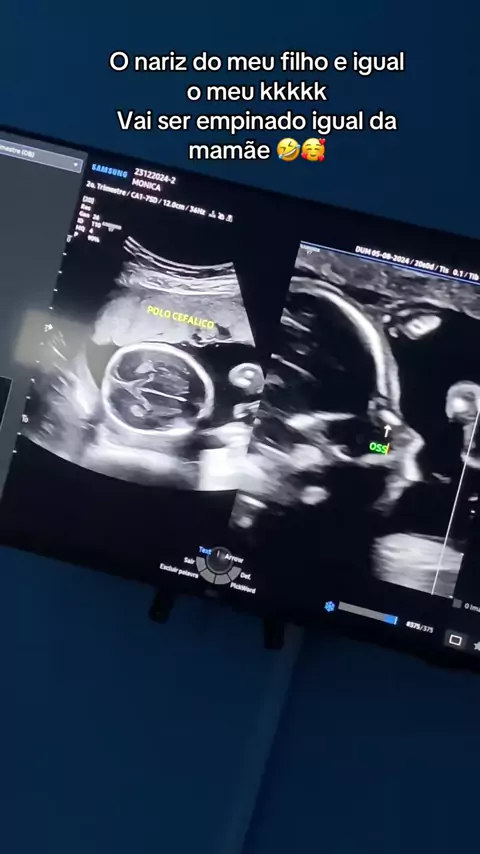

Ultrasom 10 semanas e 1 dia! 💙#bebearcoiris🌈 #gestante #mamaesno #maedeprimeiraviagem #gestacao #bebearcoiris👶🌈 #maedemenino #gestante #mamaes #mamaedeprimeiraviagem #mamaedeprimeiraviagem #gravidasno #testedeovulacao #mamae